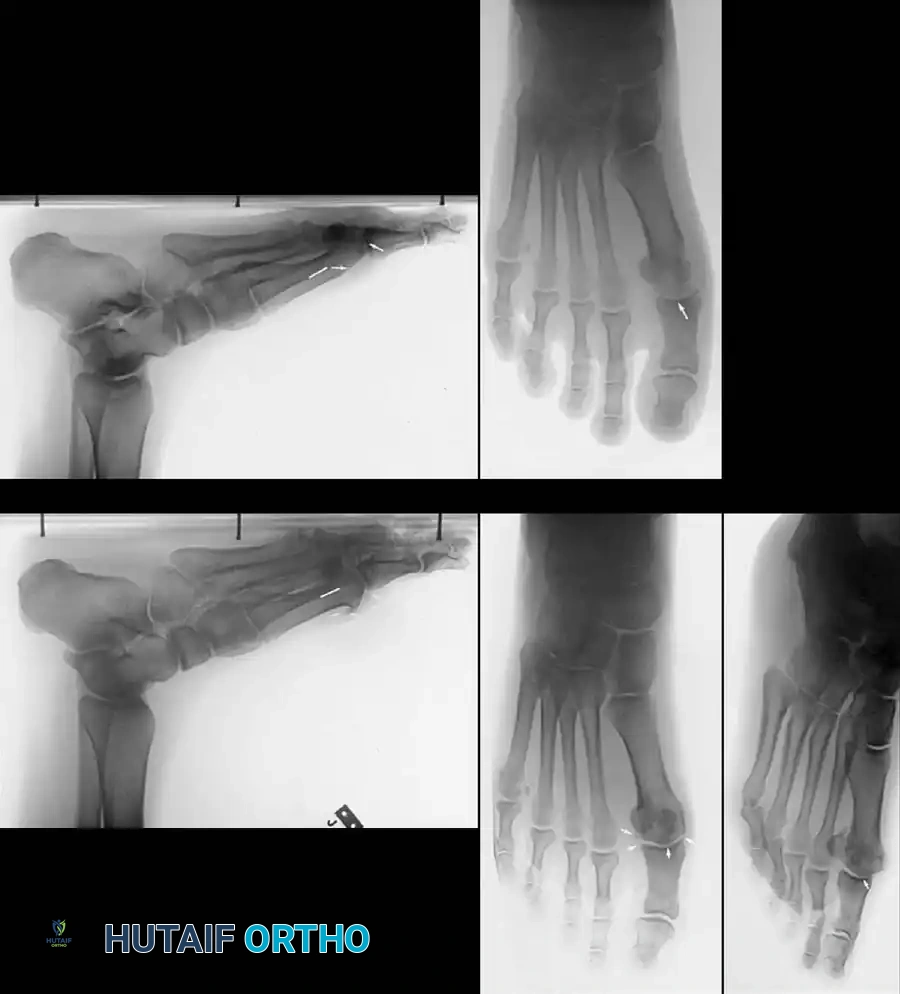

Associated Surgical & Radiographic Imaging